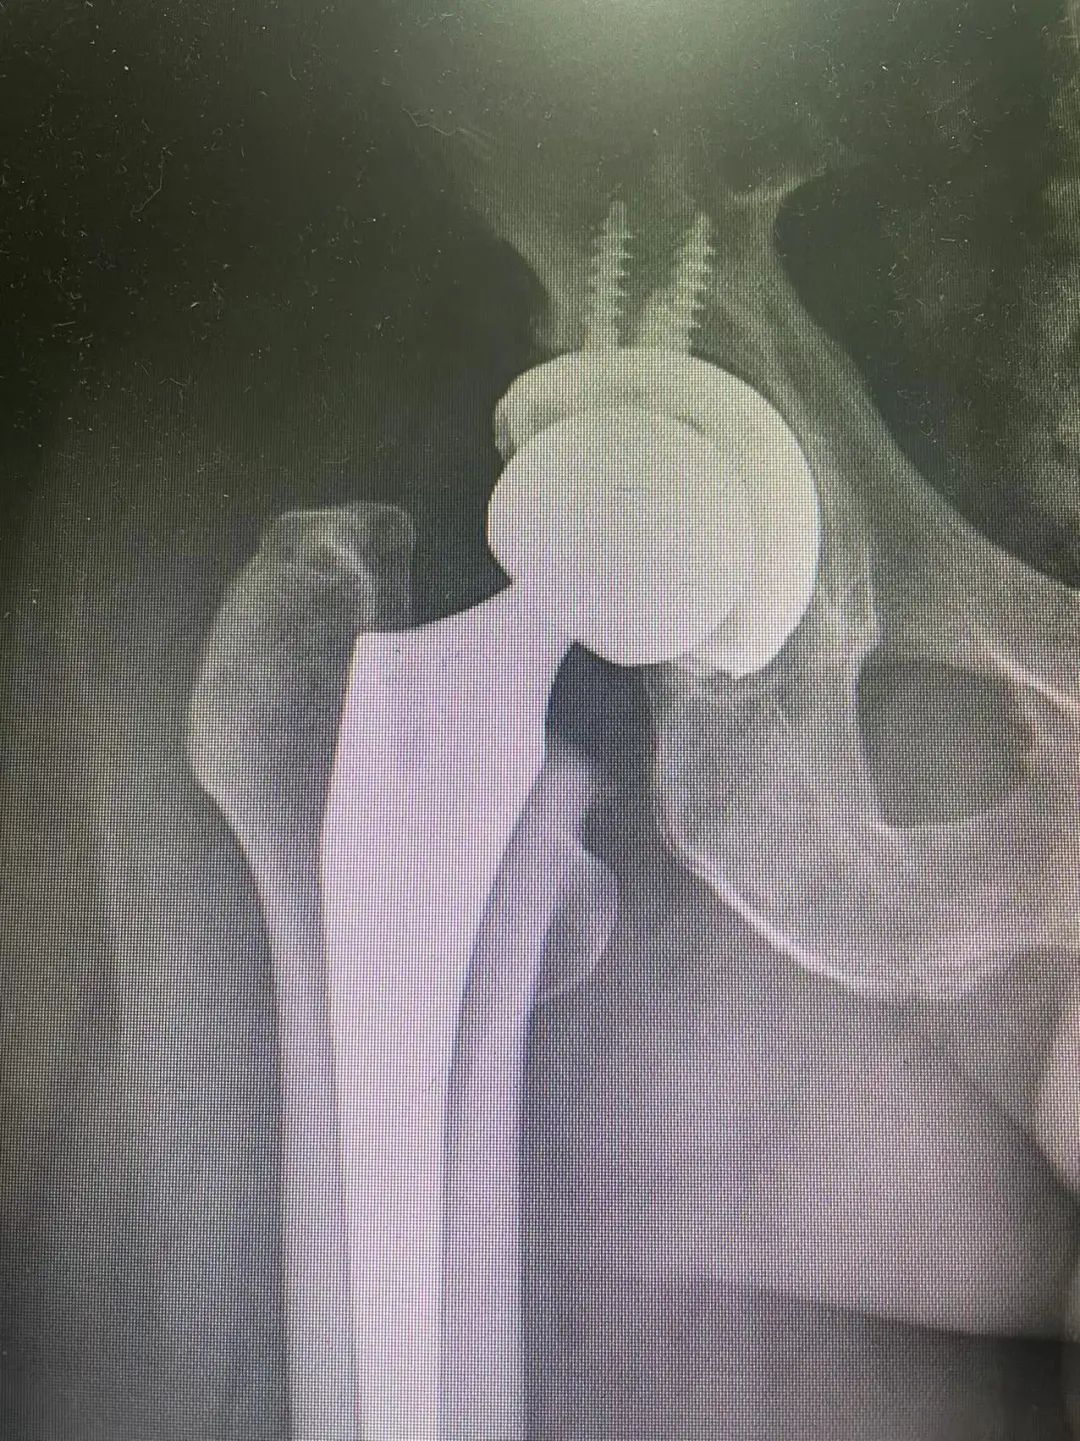

髋臼假体位置的准确测量对于评估全髋关节置换术后的预后具有重要意义。平片和CT扫描已被用来评估它的位置。结果表明,使用CT可以准确评估部件的位置;然而,由于CT扫描昂贵且使患者暴露在大量辐射中,x光平片仍被广泛使用。

为降低THA术后的脱位率,Lewinnek提出臼杯安全区的概念:影像学前倾角 (15±10°),外展角(40±10°),在安全区内的脱位率为1.5%,在安全区外的脱位率为6.1%,虽有争议但得到大多数学者认可。